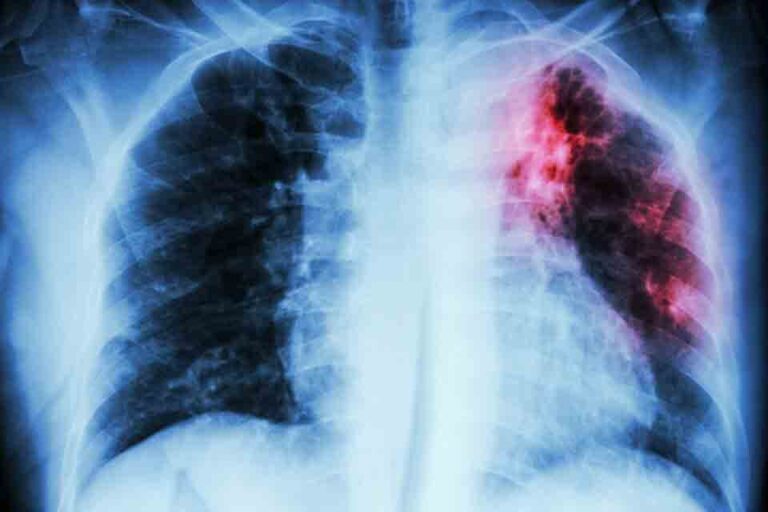

Безгак — ўткир юқумли касаллик бўлиб, анопҳелес чивини орқали юқиши, қалтираш, тана ҳароратининг кўтарилиши, талоқ ва жигар катталашиши ҳамда камқонлик билан характерланади....

Ушбу касалликнинг ўта хавфли касаллик саналиши, озгина эътибосизлик билан қаралиши эса ҳатто инсонлар ўлимига олиб келиши боиси...